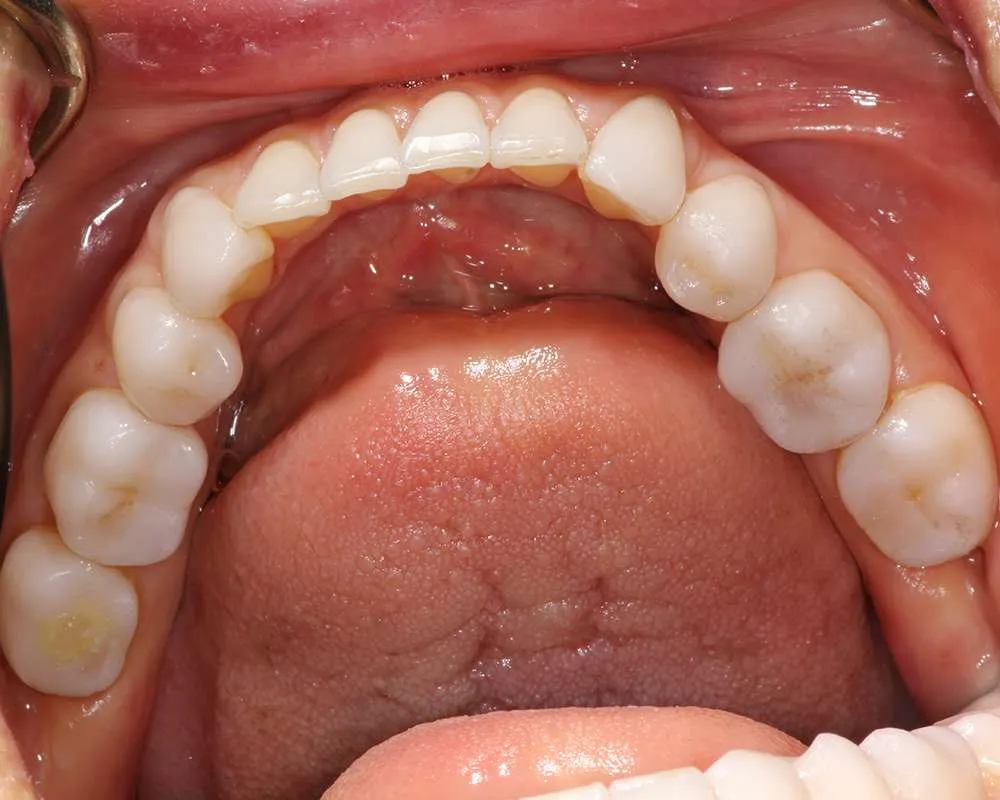

Real Stories, Real Results: Case Studies Showcasing How Our Personalized Approach Transforms Smiles and Lives

Complex Cases

Witness the Remarkable Changes We Can Achieve